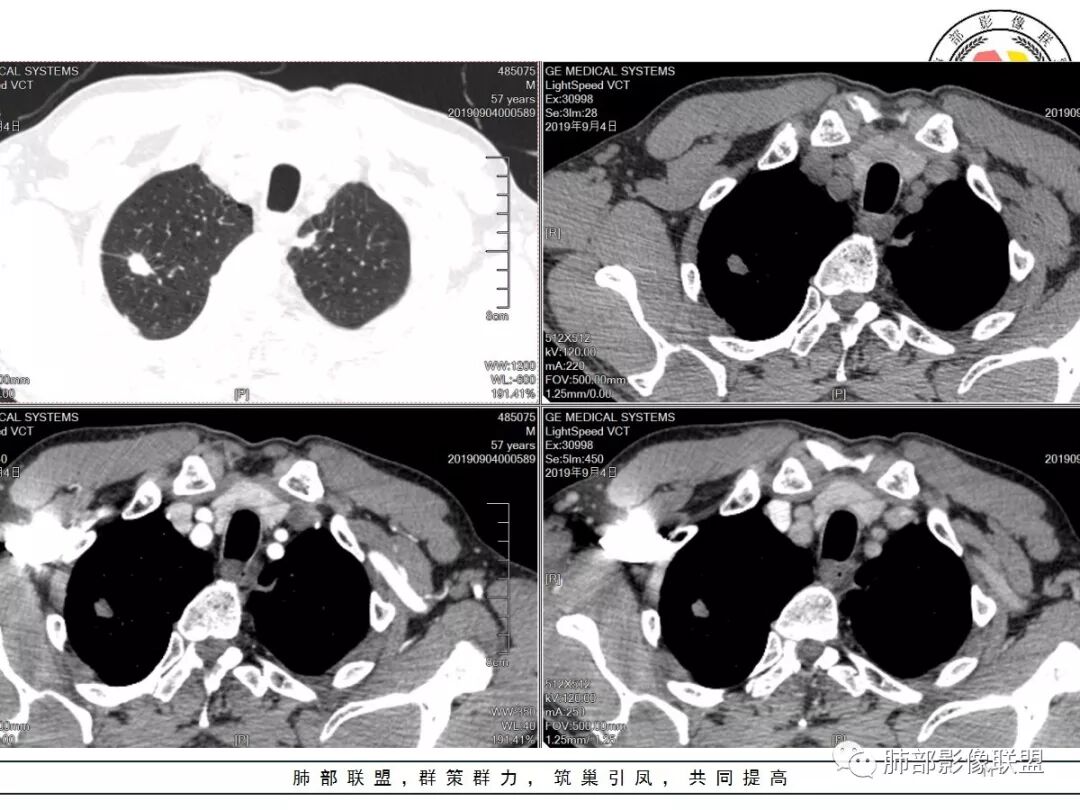

男,57岁,因“体检发现右上肺占位”入院。凝血常规、血常规、肾功能等均未见明显异常。

CT值:

平扫  18                          动脉期  28                      静脉期 41

右肺尖结节边缘可见卫星灶,结节边缘平直凹陷、长毛刺,外观上有炎性结节的特点

增强扫描右肺尖结节强化不明确,但左肺尖后段结节出现了典型的环形强化

右肺上叶结节灶,边缘膨隆,有毛刺,胸膜牵拉,轻度强化,左肺上叶结节灶环形强化,左肺考虑结核,右肺结节灶,不排除疤痕癌。

两上肺(右尖左尖后)都有小结节影,右肺尖结节边缘可见卫星灶,结节边缘平直凹陷、长毛刺,部分膨隆,增强扫描右肺尖结节强化不明确;左肺尖后段结节边缘平直凹陷,增强见环形强化。考虑结核可能性大,右上肺注意鉴别腺癌。

右肺上叶尖段结节,边缘平直收缩,周围有细长毛刺,有卫星灶,符合结核,但有静脉期轻度强化,结核应该没有强化,肺癌?

双肺尖结节 左肺边缘收缩 环形强化 右肺病灶上部边缘平直及长毛刺 下部分边缘膨隆及分叶 细短毛刺 好像有局灶强化 不除外结核基础上的瘢痕癌可能

倾向二元,左肺上叶病灶环形强化支持结核,右肺上叶结节平直、部分稍膨隆,胸膜牵拉征,部分毛刺粗短、支气管似乎边缘截断,临近小叶间隔增厚,延迟强化,密度似乎不均匀,内见小点状坏死,腺癌放前面,炎性放待排。

左上叶结节,环形强化,考虑肉芽肿病变,结核可能,右上叶结节,中度强化,有长毛刺,胸膜牵拉,有刀切征,考虑肉芽肿病变,腺癌待排,建议抗炎后复查或穿刺活检。

南边:

有炎性的特点,但是确实存在恶性征象

我觉得恶性最起码不能排除,要考虑,最起码要建议临床干预

一般我的观点:多发炎性征象,如果合并有恶性征象,就不能排除恶性